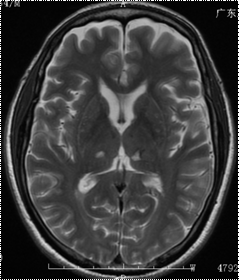

颅脑MRI提示:双侧基底节、放射冠区多发腔隙性脑梗死(如图一);颈部血管彩超提示:双侧颈动脉重度狭窄。3D-ASL提示:右侧额叶局部灌注减低,感兴趣区CBF测值为(28.39±12.97)mL/100g/min,低于对侧镜像感兴趣区测值(57.15±13.80)mL/100g/min(如图二)。DSA示:1、双侧颈内动脉起始部重度狭窄,狭窄程度均约90%,右侧狭窄长度约8mm(如图三);2、左侧颈总动脉末端中度狭窄,狭窄程度约50%,狭窄长度约1.0cm(如图四)。

图一